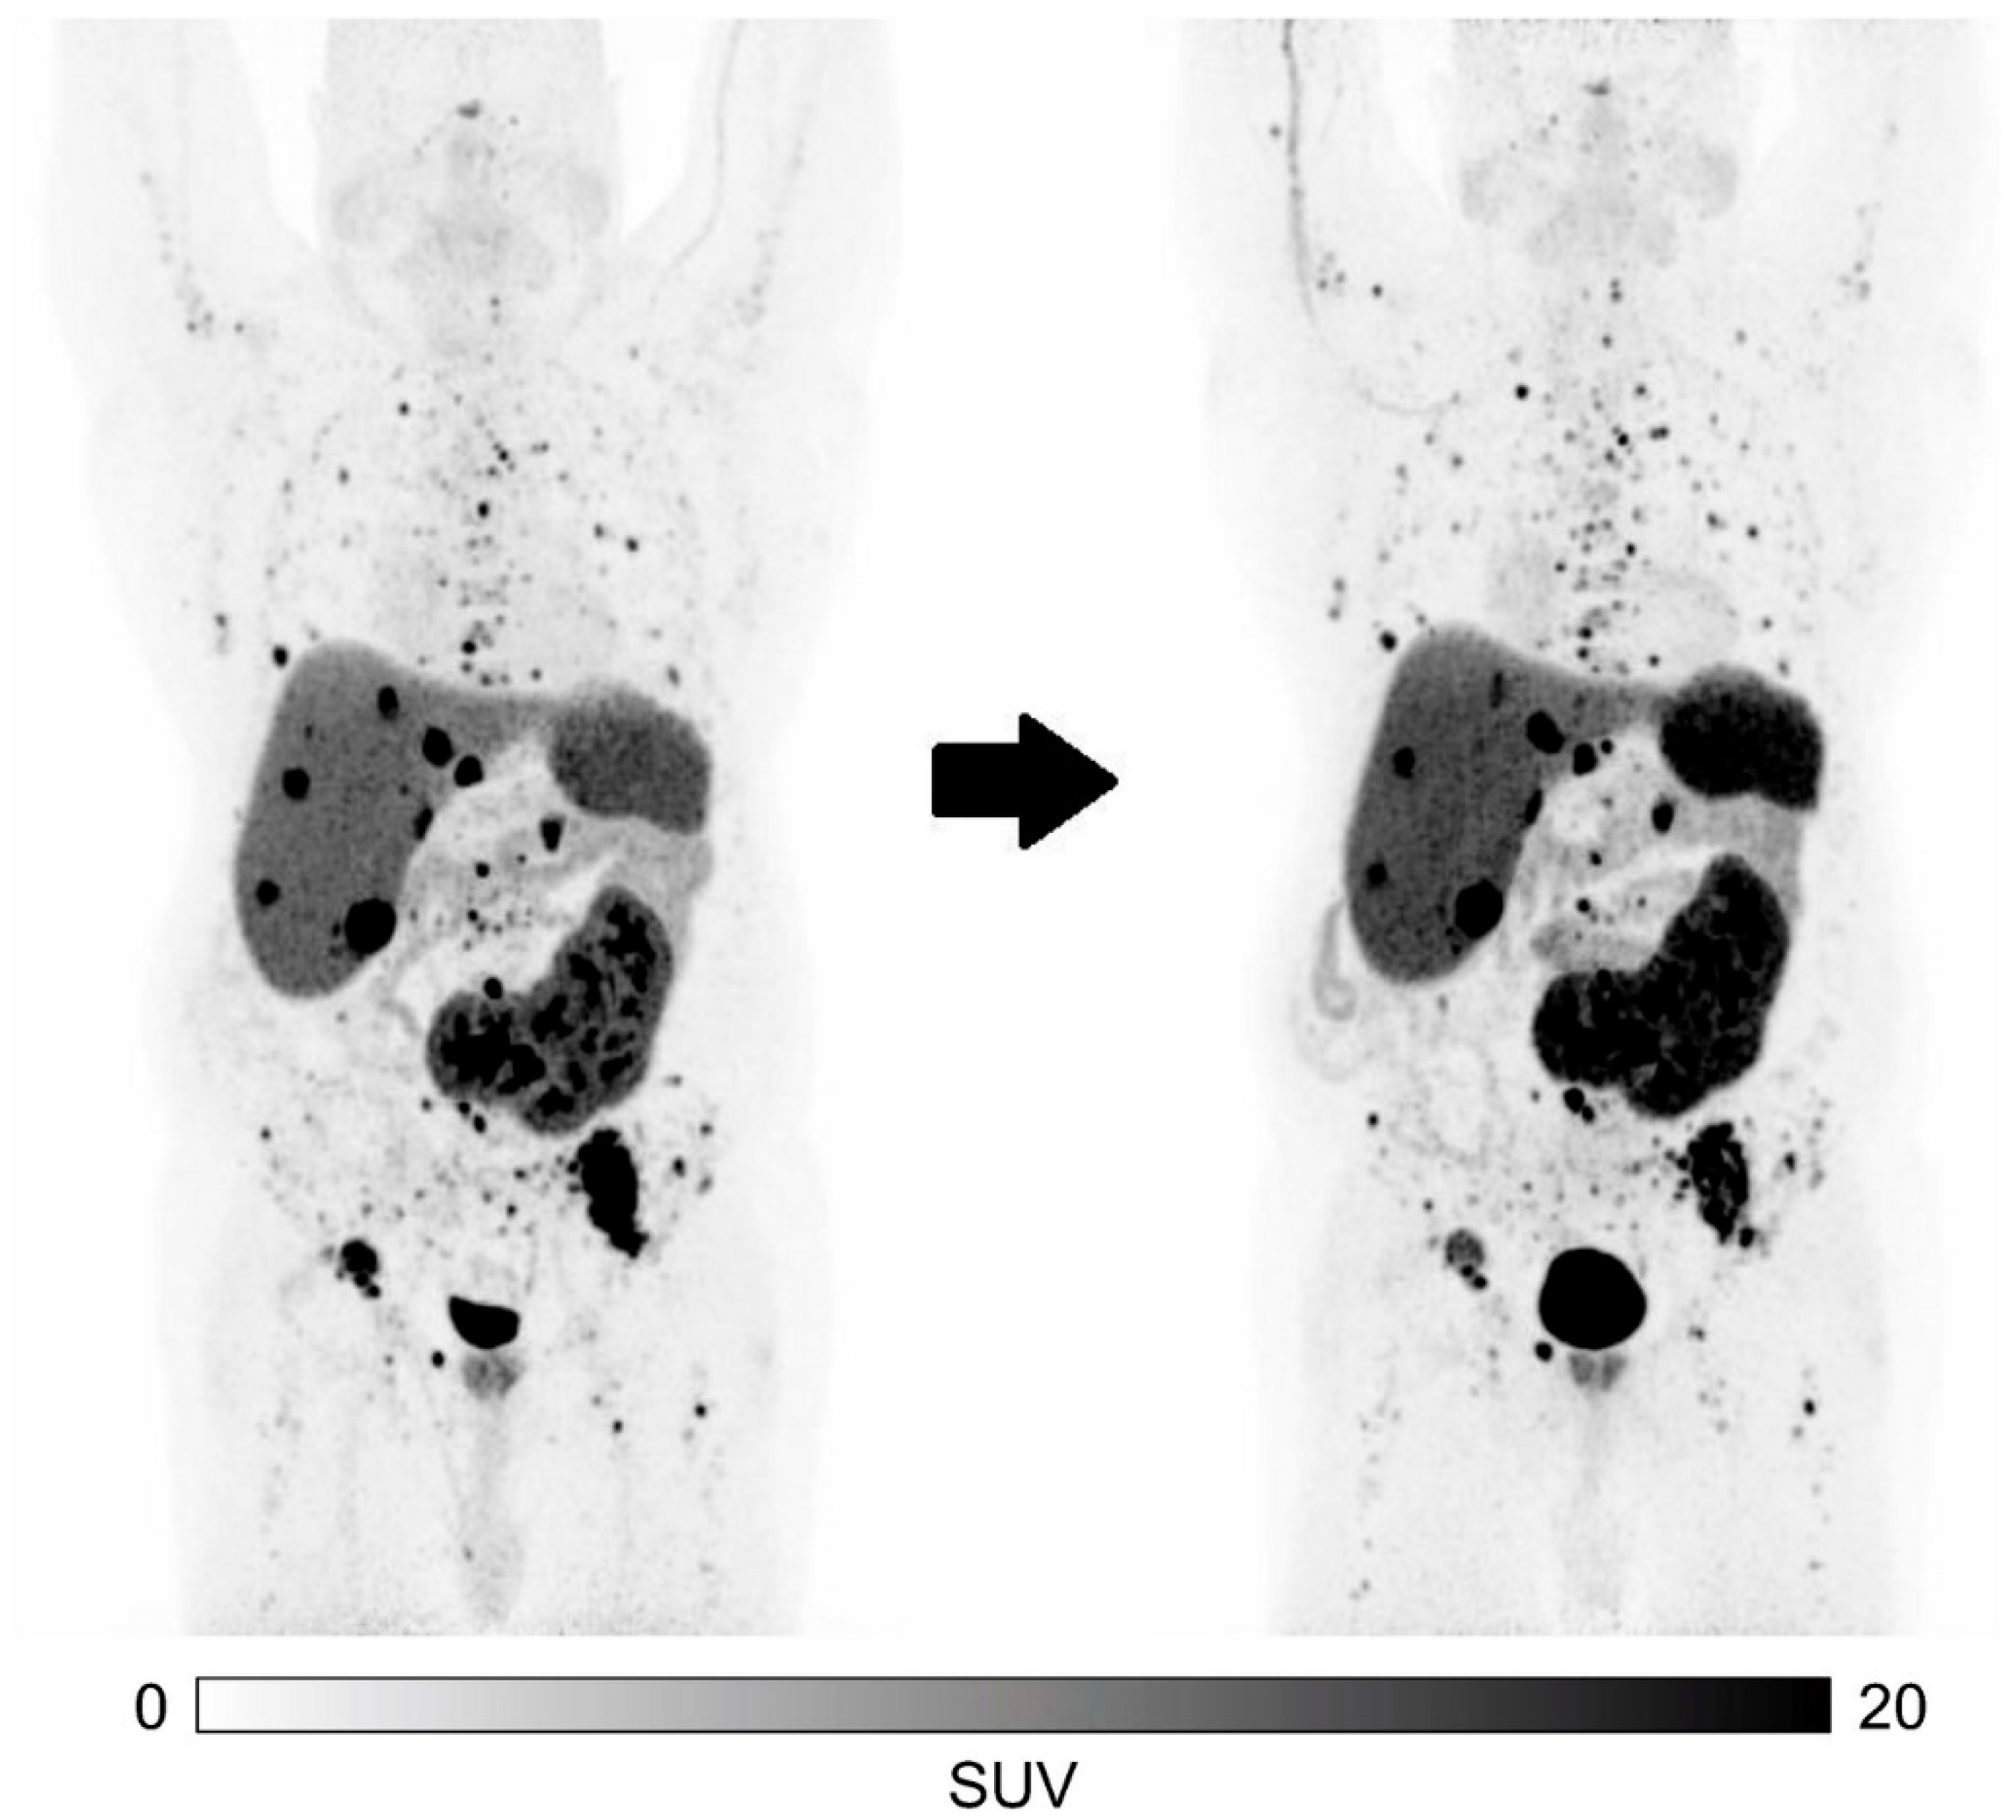

- Ballal, S.; Yadav, M.P.; Bal, C.; Sahoo, R.K.; Tripathi, M. Broadening horizons with 225Ac-DOTATATE targeted alpha therapy for gastroenteropancreatic neuroendocrine tumour patients stable or refractory to 177Lu-DOTATATE PRRT: First clinical experience on the efficacy and safety. Eur. J. Nucl. Med. Mol. Imaging 2020, 47, 934–946. [Google Scholar] [CrossRef]

- Ballal, S.; Yadav, M.P.; Tripathi, M.; Sahoo, R.K.; Bal, C. Survival Outcomes in Metastatic Gastroenteropancreatic Neuroendocrine Tumor Patients receiving Concomitant 225Ac-DOTATATE Targeted Alpha Therapy and Capecitabine: A Real-world Scenario Management Based Long-term Outcome Study. J. Nucl. Med. 2023, 64, 211–218. [Google Scholar] [CrossRef]